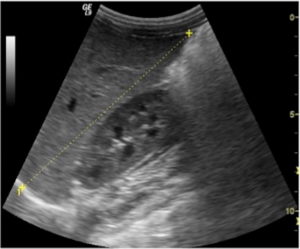

- Кистозные образования. Имеют вид анэхогенных (чёрных полностью) образований или пятен. Контуры у таких кист ровные, а форма округлая. При кистах сигнал ультразвука усиливается.

Предопухолевые процессы могут быть доброкачественные, которые сохраняются на протяжении всей жизни человека, при этом в редких случаях перерождаются злокачественные. Такие новообразования в почке на УЗИ имеют нечёткие границы, желеобразной консистенции или представляют собой скопления из жировых клеток.

При обнаружении рака почки на УЗИ специалист может увидеть варикоцеле, что свидетельствует о прорастании метастазами венозных сосудов. Опухоль почки на УЗИ проявляет себя в виде деформации контура органа, наличия признаков некроза и инфаркта тканей.

Довольно тяжело диагностировать анэхогенное образование в почке на УЗИ, вследствие пониженной плотности её содержимого. При УЗДГ почек оно имеет изображение в виде тёмного пятна, свидетельствующее о кровоизлиянии в орган.